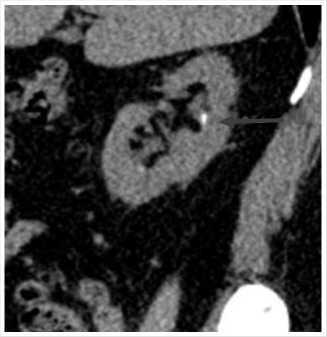

Рис. 1. МСКТ в нативном режиме, сделанная в марте 2023 г. Стрелками указаны конкремент ЛМС справа (с наличием расширения ЧЛС) и ЛМС слева.

10,9 ммоль/л, креатинин 124 мкмоль/л, мочевая кислота 445 мкмоль/л, пациентке рекомендовано выполнение анализа суточной мочи и низкодозная КТ органов мочевыделительной системы в нативном режиме. Диагностирована выраженная гиперурикурия до 870 мг, по данным КТ выявлено: Чашечно-лоханочная система (ЧЛС) справа расширена: чашечки до 17 мм, лоханка до 44 x 16 мм, в нижней группе чашечек правой почки определяются три конкремента, размерами до 4 мм, плотностью до 420 HU, в лоханке правой почки определяется крупный конкремент, размерами до 15 x 9,5 мм плотностью до 550 HU, мочеточник справа при нативном исследовании без значимого расширения, конкрементов в нем достоверно определяется. Вместе с тем, отмечается уплотнение клетчатки на уровне ЛМС справа, а также по ходу верхней трети мочеточника, где визуализируются лимфатические узлы, расположенные парааортально, максимальными размерами до 19 x 7 мм. ЧАС левой почки не расширена. Однако, отмечается наличие мелкого конкремента в области лоханочно-мочеточникового перехода, размерами до 4,8 x 3,5 мм, плотностью до 351 HU (Рис. 1, 2). Предложена госпитализация для проведения оперативного вмешательства по срочным показаниям с целью дренирования правой почки, от чего пациентка отказалась. Учитывая данные суточного анализа мочи, наличие конкрементов верхних мочевых путей (ВМП) относительно низкой плотности, заподозрен мочекислый (уратный) нефролитиаз. От проведения литолитической терапии в амбулаторных условиях пациентка также отказалась.